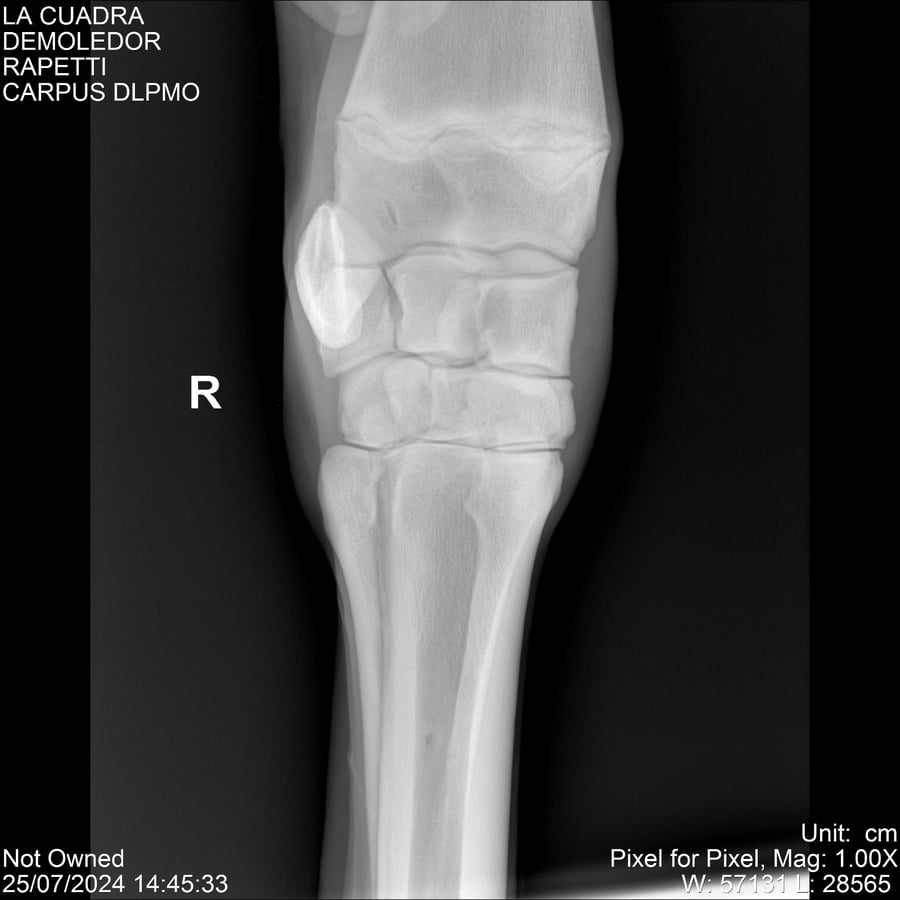

LOTE 14, DEMOLEDOR 🔥 🔥 🔥 Lote Anterior Volver al remate Lote Siguiente Ficha Contacto Montevideo - Ficha del Lote Identificador: #284454 Categoría: Yeguarizos Montevideo - 89 Visualizaciones ClicData Contacto Empresa: Abelenda N. R., Walter Hugo Nombre*: Teléfono* : E-mail* : Mensaje Enviar Registrese gratis Este contenido Exclusivo está disponible sólo para usuarios registrados Ingresar